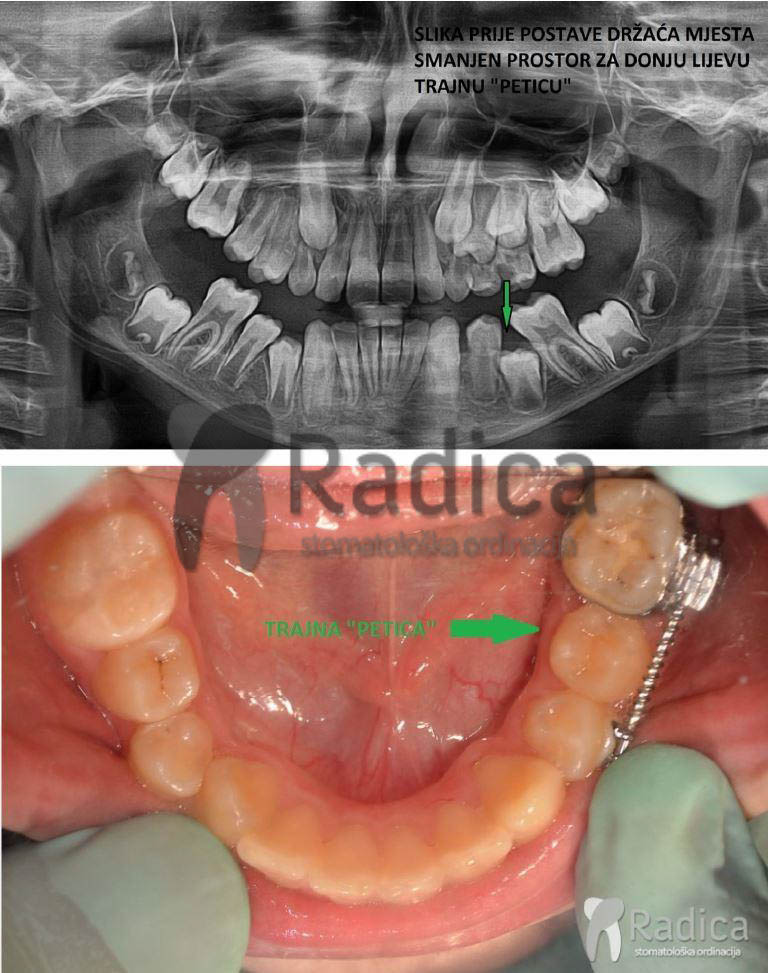

Prerano izgubljen mliječni zub uzrokuje gubitak mjesta za trajnoga nasljednika. Stoga nastaje gužva ili čak neki zubi nemaju gdje niknuti pa ostaju u kosti – nastaje anomalija koju nazivamo sekundarna kompresija.

Najčešće su to zubi koji se zadnji pojavljuju u čeljusti – gornji očnjaci i donji drugi premolari – „petice“.

U sljedećim primjerima su pokazani takvi slučajevi:

U slučaju da ipak dođe do preranog gubitka mliječnih zuba preporučuje se napraviti držače mjesta, transplatinalni i/ili lingvalni lukovi koji sprječavaju pomak „šestica“ i čuvaju mjesto za trajne nasljednike.